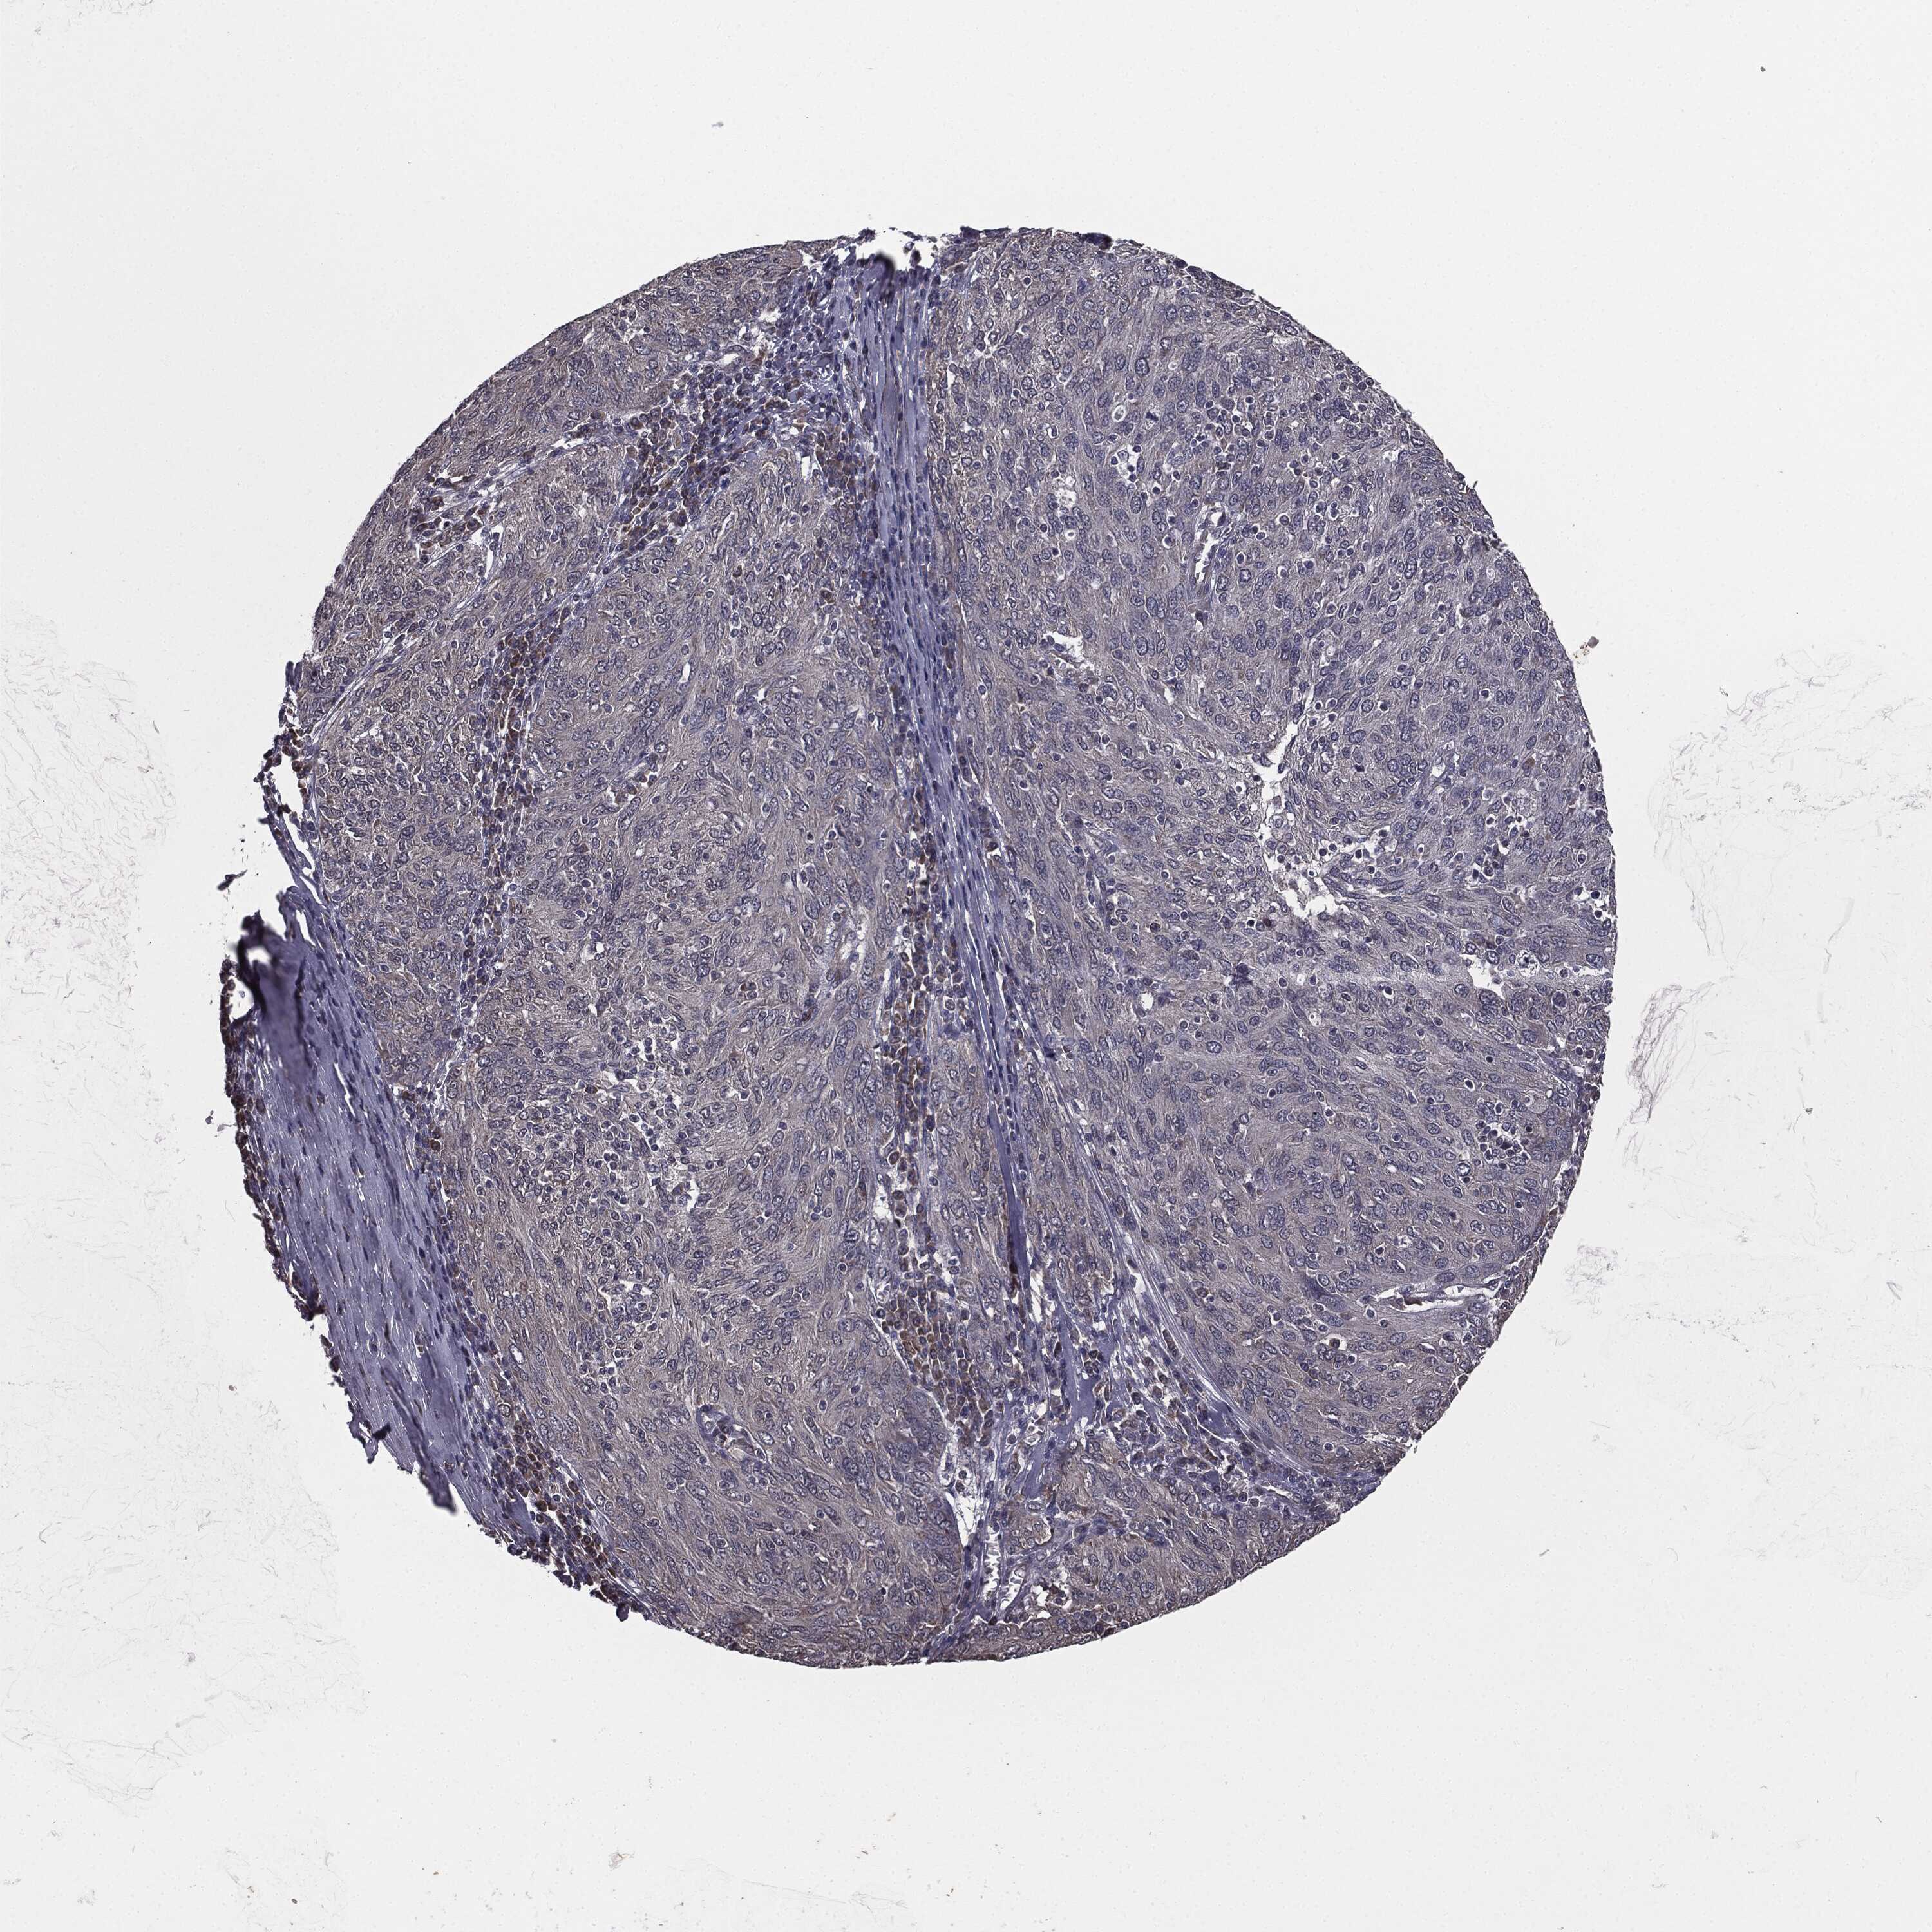

OVARIAN CANCER - Protein expressioni

A mouse-over function shows sample information and annotation data. Click on an image to view it in a full screen mode. Samples can be filtered based on level of antibody staining by selecting one or several of the following categories: high, medium, low and not detected. The assay and annotation is described here.

Note that samples used for immunohistochemistry by the Human Protein Atlas do not correspond to samples in the TCGA dataset.

Antibody stainingi

Antibody staining in the annotated cell types in the current human tissue is reported as not detected, low, medium, or high, based on conventional immunohistochemistry profiling in selected tissues. This score is based on the combination of the staining intensity and fraction of stained cells.

Each image is clickable and will lead to virtual microscopy that enables deeper exploration of all samples and also displays staining intensity scores, fraction scores and subcellular localization as well as patient and tissue information for each sample.

Antibody HPA052606

Cystadenocarcinoma, serous, NOS